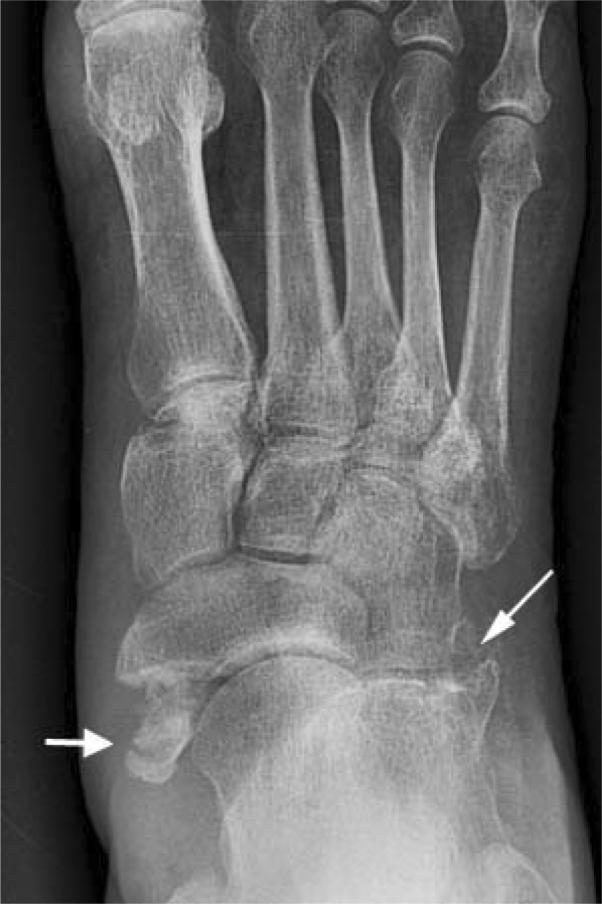

A 62-year-old woman with severe seizure disorder presented with right ankle and foot pain after being found down, presumably following a seizure recurrence. Imaging showed an acute comminuted fracture of the anterolateral aspect of the right calcaneus, as well as an acute avulsion fracture of the right navicular tuberosity at the site of insertion of the tibialis posterior tendon. This fracture pattern suggests forced abduction of the midfoot or forefoot with severe compression of the lateral column and failure of the medial column under tension, an entity that has previously been described as the nutcracker fracture. This mechanism of injury should prompt particularly careful evaluation of the navicular, cuboid, and calcaneus for any signs of injury. Subtle fractures of the navicular and calcaneus may be overlooked in the emergency setting, leading to a delay in surgical treatment and ultimately chronic foot deformities that can result in significant functional disability.